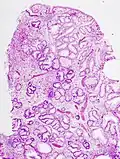

- Микроструктура полипов желудка

Гиперпластический полип -